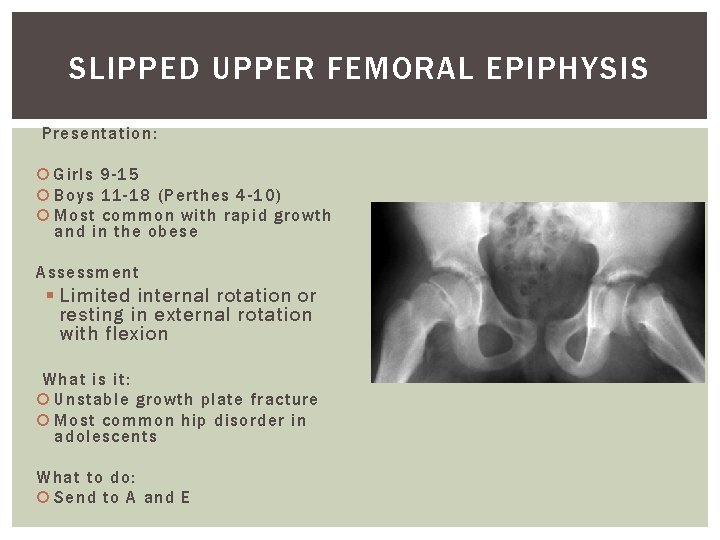

SLIPPED UPPER FEMORAL EPIPHYSIS Presentation: Girls 9 -15 Boys 11 -18 (Perthes 4 -10) Most common with rapid growth and in the obese Assessment § Limited internal rotation or resting in external rotation with flexion What is it: Unstable growth plate fracture Most common hip disorder in adolescents What to do: Send to A and E